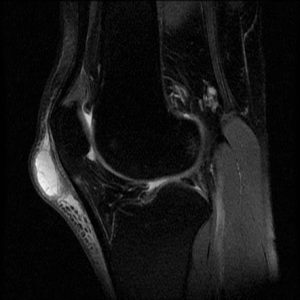

A finding on plain film x-ray may be a thickening of the soft tissue anterior to the patellar ligament. This is demonstrated on a lateral view of the knee (Figure 1). When it is this prominent, there may be an actual palpable mass. When less fluid is present, there may be a puffiness over the ligament that may be palpable.

Figure 1